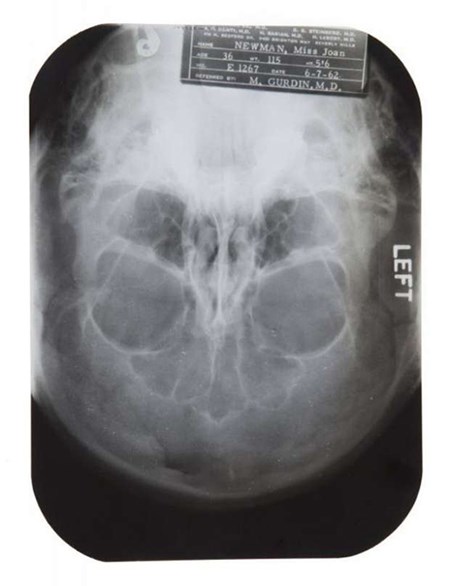

وبيعت بعض الملفات الطبية الخاصة بمارلين مونرو التي تثبت أن الأسطورة الهوليودية خضعت لعمليات تجميل عدة في شبابها، حيث تمَّ عرض ملفات تثبت إجرائها لعدة عمليات تجميل وذلك في مزاد دار "جوليينز"، وأظهرت الملفات أنَّها غيرت ذقنها وطرف أنفها اعتبارًا من العام 1950 عندما كانت في سن الرابعة والعشرين.

كما صبغت مونرو شعرها باللون الذهبي بصفة مستمرة، بينما كان أسود اللون في الحقيقة، حيث قال جراح التجميل الشهير في نيويورك مايكل جوردن، إنَّ أيقونة هوليوود خضعت لمشرط الجراح لأسباب تجميلية.